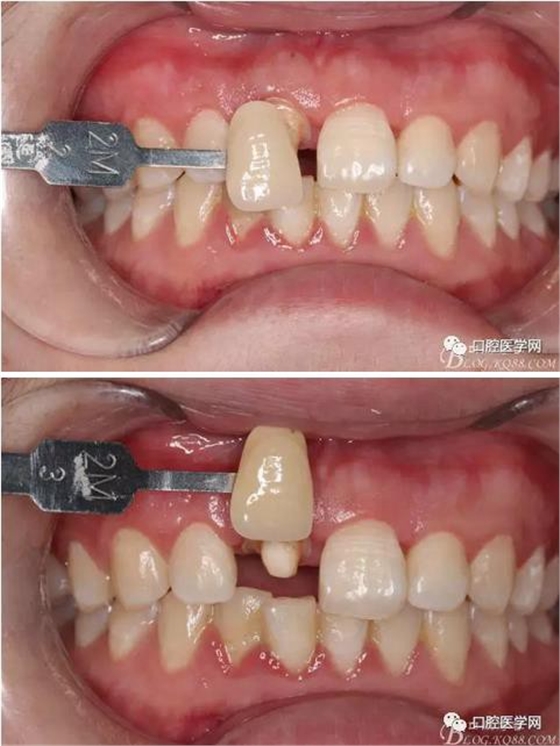

術(shù)前口內(nèi)照,11殘根,唇側(cè)牙齦紅腫,肩臺(tái)在齦下2毫米,舌側(cè)正常.21有被動(dòng)萌出,長(zhǎng)寬比例不協(xié)調(diào)??谇恍l(wèi)生一般,有菌斑。

術(shù)前原有牙冠復(fù)位,牙齦紅腫。

比色